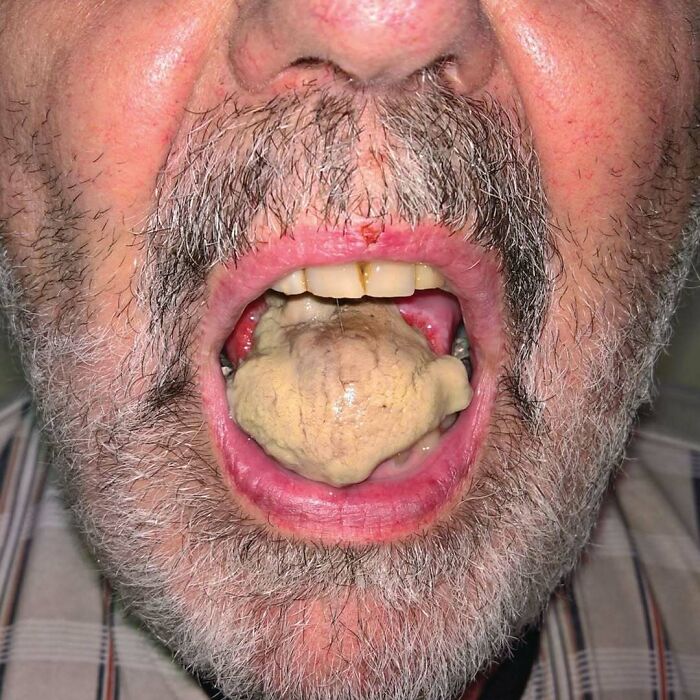

A 50-year-old woman presented to the dental clinic with a 10-day history of tongue and inner cheek pain. She had a history of Crohn’s disease, for which she had been previously treated with prednisone and mesalamine. At this presentation, she had no gastrointestinal or systemic symptoms. On physical examination, she had numerous painful, shallow erosions that merged to form linear “snail track” formations on the dorsal tongue and buccal mucosa. There were no skin lesions. Laboratory studies revealed an absolute eosinophil count of 870 per cubic millimeter (reference range, 50 to 500). A biopsy specimen of the dorsal tongue showed intraepithelial microabscesses with neutrophils and eosinophils, findings consistent with a diagnosis of pyostomatitis vegetans.

Pyostomatitis vegetans is a very rare oral manifestation with unknown pathogenesis. Skin and other mucous membrane involvement may be seen. This lesion has strong association with Inflammatory Bowel Disease (IBD) and may be the first sign of it. The management of Pyostomatitis vegetans is usually based on the management of underlying bowel disease.

The patient was referred for gastroenterologic evaluation, and her bowel disease was found to be quiescent. The oral lesions were treated with topical glucocorticoids and benzocaine. At 1 month of follow-up, her symptoms had resolved, and they did not subsequently recur.